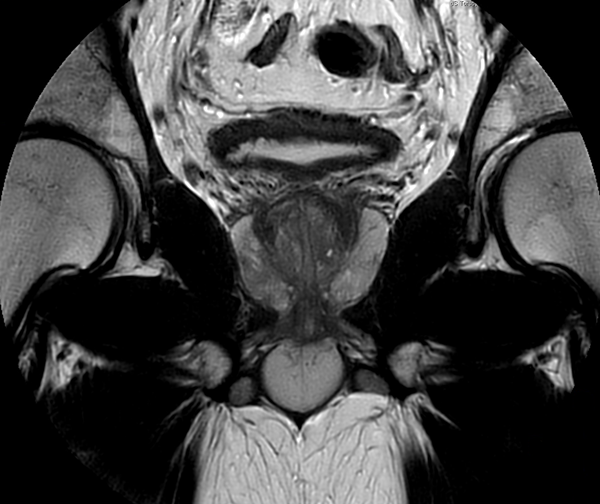

Motion-free Prostate imaging